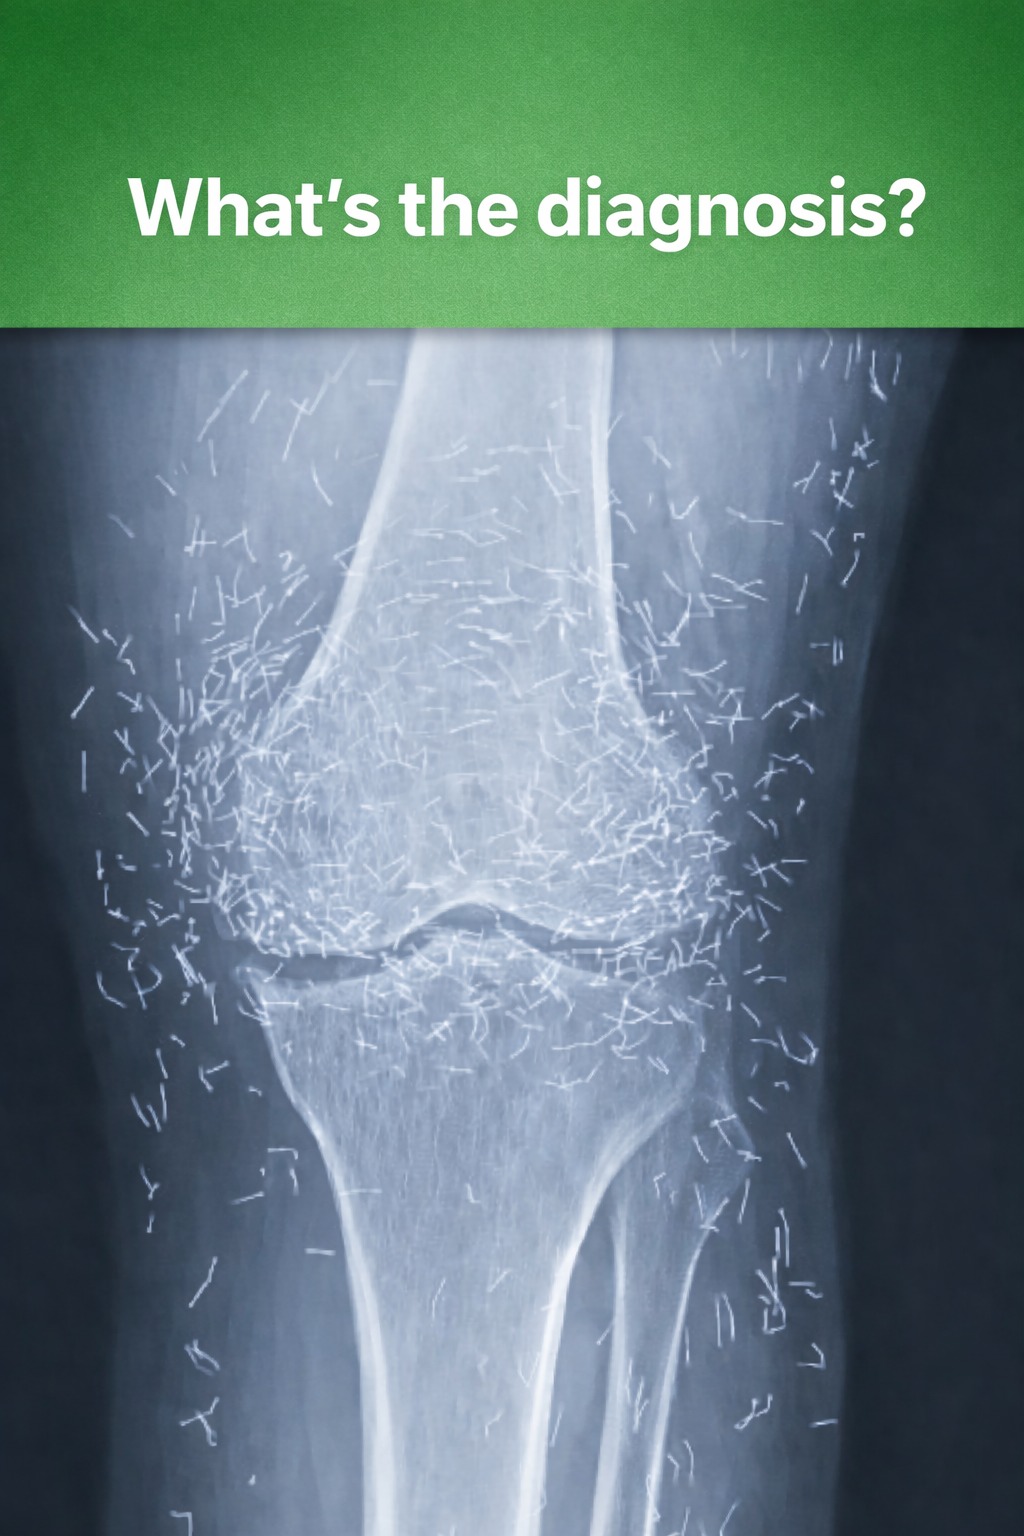

A 65-year-old woman came to the clinic after experiencing months of chronic knee pain. Despite trying multiple treatments including traditional Chinese medicine she found no relief. This X-ray was taken during her visit. What do you think is the diagnosis. 🦴 Answer in the comments 👇🏼

Doctors Discover Unexpected “Gold Mine” in Woman’s Knees When a 65-year-old woman in South Korea visited doctors for chronic knee pain, they discovered something unexpected — dozens of tiny gold acupuncture needles embedded around her knees. The unusual finding quickly drew attention in the medical world. The woman had long struggled with osteoarthritis, a condition…